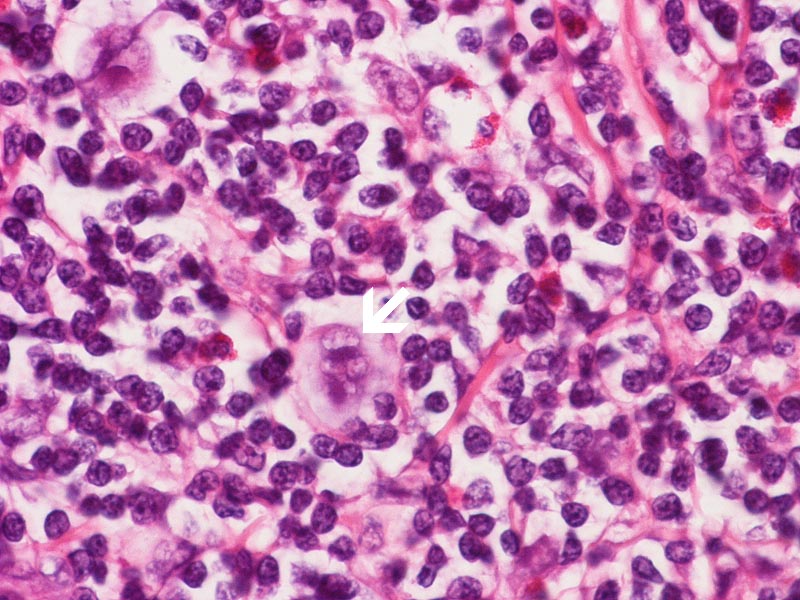

This is high magnification images taken from other areas of this case. Note the Hodgkin cells (arrow).

• Reed-Sternberg (RS) cells: Classical diagnostic Reed-Sternberg are large cells with abundant basophilic cytoplasm and must have at least two nuclear lobes or nuclei. The nuclei are large and often rounded in contour and have a prominent eosinophilic nucleolus. Diagnostic RS cells must have lat least two nucleoli in two separate nuclear lobes. These cells, however, do not need mirror-image double nuclei to be classified as Reed-Sternberg cells. Classical

• Hodgkin cells are uninuclear version of Reed-Sternberg cells.

• Mummified cells are large necrotic cells with deep eosinophilic cytoplasm and contracted contour. The nuclear details are also lost.